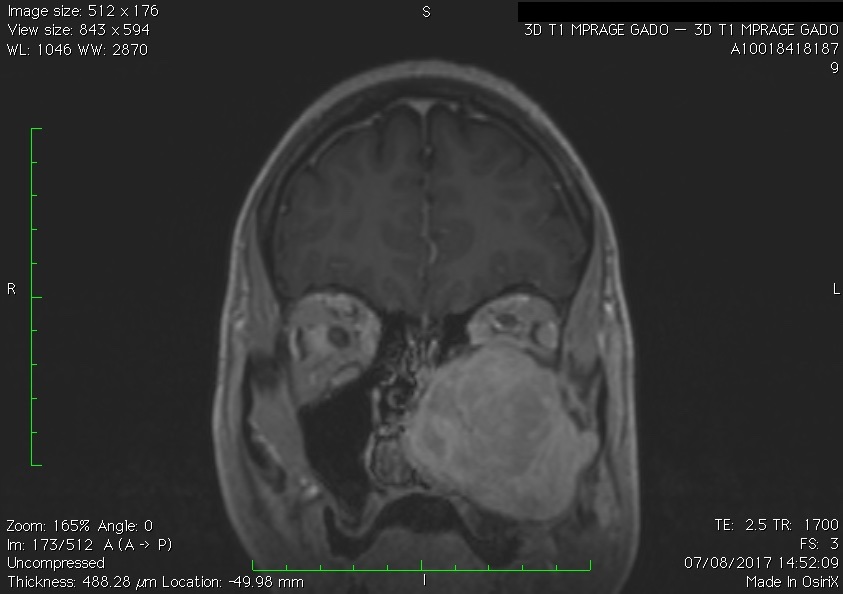

Les neurinomes de l’acoustique

Ce sont des tumeurs bénignes à croissance lente développées au dépens du nerf vestibulaire reliant l’oreille au cerveau. Aussi appelé schwannomes vestibulaires, ces tumeurs peuvent croître et endommager le tronc cérébral et les nerfs crâniens adjacents lors de leur développement. Les symptômes comprennent des troubles de l’équilibre ou des instabilités, une perte auditive et/ou des bourdonnements (acouphènes) dans l’oreille affectée.

Le traitement comprend la surveillance radiologique, la chirurgie ou la radiothérapie stéréotaxique. La chirurgie est réalisée par les membres de l’équipe du service ORL spécialisés dans cette chirurgie. Ensemble, ils décident de la meilleure façon d’aborder et enlever la tumeur tout en préservant la fonction nerveuse du visage. Un surveillance de la de la fonction du nerf faciale (monitoring) est effectuée pendant toute la durée de la chirurgie.

Une autre option de traitement réside dans la radiochirurgie stéréotaxique, un type de radiothérapie qui peut concentrer les rayons X à haute puissance sur la tumeur.

Différents stades du neurinome (d’après Jackler, ATLAS OF SKULL BASE SURGERY & NEUROTOLOGY. Thieme. ©2009)